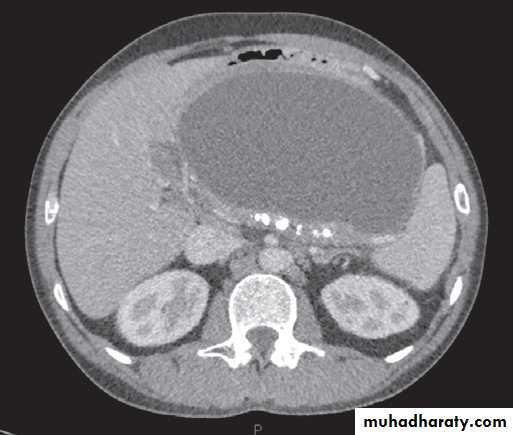

Normal pancreas in a post contrast CT

CT showing large pancreatic pseudocyst (C) compressing the stomach (S). The pancreas is atrophic and calcified (arrows).